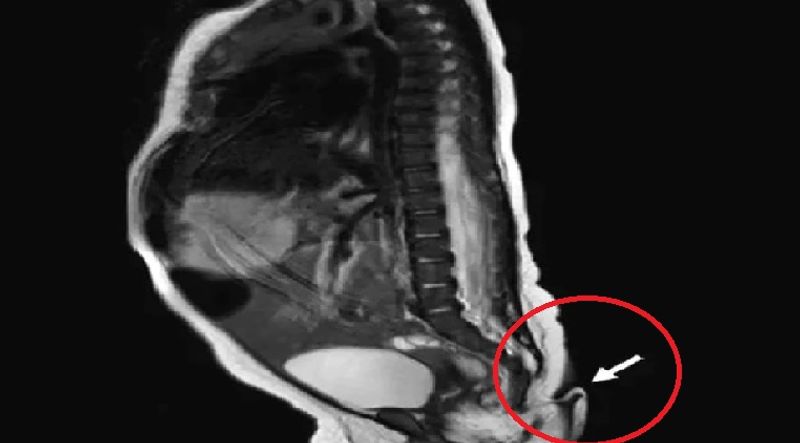

அந்த குழந்தைக்கு பின்புறத்தில் வால் இருந்துள்ளது. இதை கண்ட பெற்றோர்கள் அதிர்ச்சி அடைந்தனர். மேலும் வியப்பில் ஆழ்ந்தனர். அந்த வால் சுமார் 5.7 செ.மீ இருந்தது. மேலும் அது தோல் மற்றும் முடியால் உருவாகியிருந்தது. இதை அடுத்து மருத்துவர்கள் அந்த வாலை வலியில்லாமல் அகற்ற முடிவு செய்தனர்.

அதன்படி, குழந்தை பிறந்து இரண்டு மாதங்களுக்கு பிறகு குழந்தையின் வால் அறுவை சிகிச்சை மூலம் அகற்றப்பட்டது. இதுபோன்ற சம்பவம் உலகில் 195 பேருக்கு மட்டுமே நிகழ்ந்துள்ளது என்பது குறிப்பிடத்தக்கது. இது பெரும்பாலும் ஆன் குழந்தைகளுக்கு மட்டுமே நடக்கும் என்றும் 17 குழந்தைகளில் ஒரு குழந்தைக்கு இதனால் மூளை அல்லது மண்டை ஓடு வளர்ச்சி குறைபாடு ஏற்படும் என்றும் மருத்துவர்கள் தரப்பில் கூறப்படுகிறது.